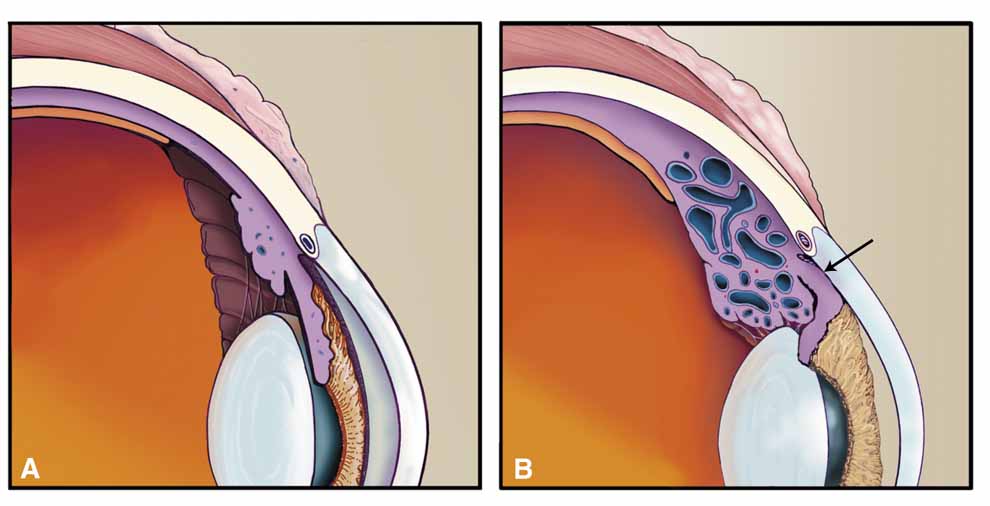

All disorders in this group have some degree of choroidal congestion (Table 6), which may be noted by the usual clinical signs of clinical moundlike or annular choroidal detachment or be completely undetected, particularly if anteriorly placed and hidden behind the iris.82 Choroidal congestion can produce forward rotation of the ciliary body, resulting in closure of the peripheral angle and a shallow but preserved central anterior chamber (Fig. 17).83 Although this may appear a contradiction of terms because choroidal detachments are usually associated with hypotony, experimental detachments of the ciliary body do not themselves result in aqueous shutdown,84 suggesting that low pressure with choroidal effusion is due to hyposecretion secondary to concurrent iridocyclitis. Continued aqueous production in the presence of a closed peripheral angle results in an acute pressure elevation. Some clinical diseases sharing this mechanism have been mislabeled “malignant glaucoma,” an unfortunate name that adds mystique and confusion to the mechanism underlying these diseases. Though we prefer the term cyclocongestive to describe those disorders sharing this mechanism, other terms have been suggested including ciliochoroidal effusion syndrome.85 Either is descriptive of the pathophysiologic mechanisms that cause this clinical presentation. Miotics and peripheral iridectomy may worsen these conditions, whereas they are a first-line choice in the treatment of primary angle-closure glaucomas. Although cyclocongestive glaucoma may initially begin by ciliary body rotation with peripheral iris blocking the trabecular meshwork, if it is left untreated or diagnosed incorrectly, permanent, chronic angle closure may result, requiring goniosynechialysis or filtering surgery for adequate pressure control. Filtration surgery may actually precipitate the disorder in some cases.86

Fig. 17 A. Normal anatomy. B. Cyclocongestive glaucoma. Scleral buckling and other conditions may obstruct vortex venous outflow, resulting in choroidal congestion and detachment. Swelling of the ciliary body rotates this structure about the scleral spur, closing the peripheral angle. Note the loss of visible angle structures. Laser iris retraction is the treatment of choice in cases resistant to conservative therapy (cycloplegics, topical corticosteroids, timolol maleate, and acetazolamide).